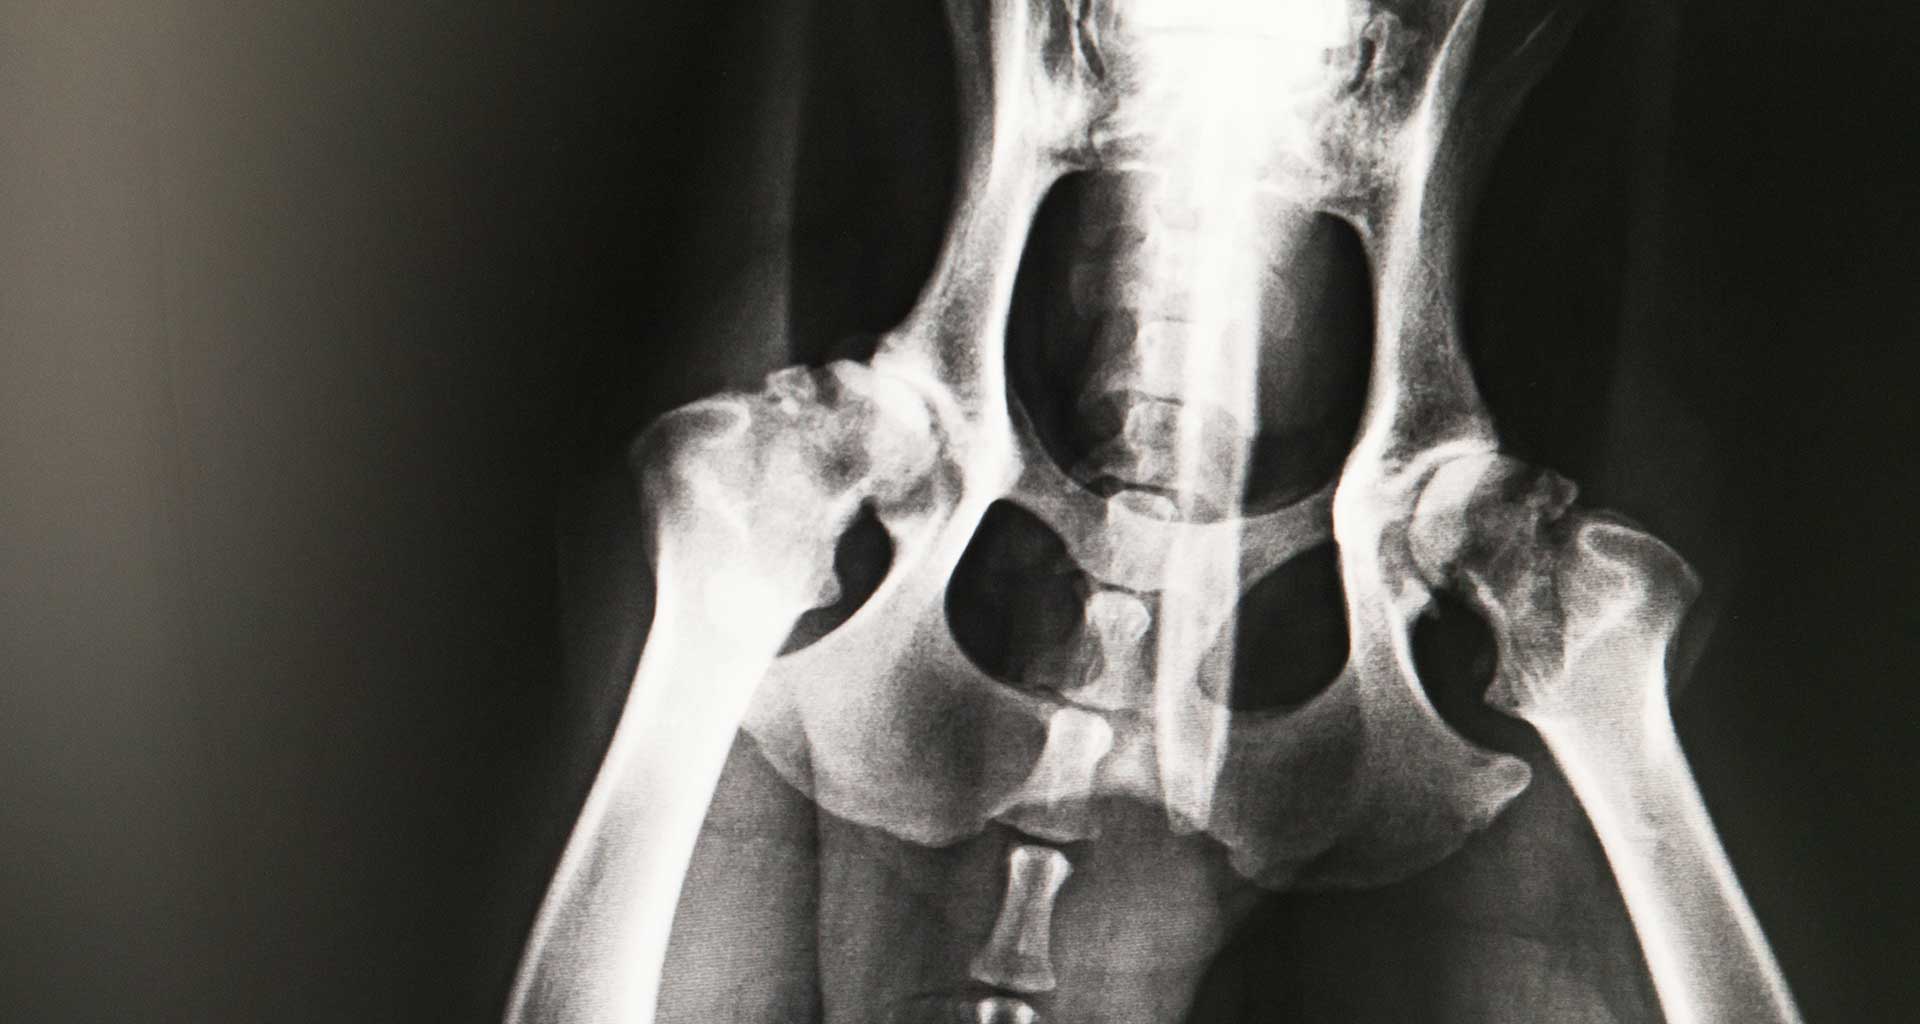

Radiographs (X-rays) are extremely important for accurate diagnosis and ruling out causes of certain diseases. Our vet clinic has skilled professionals who are able to use this technology to find the best solutions to your pet’s condition, often with near immediate results. rnrnThe main use of radiology is to determine if your pet is suffering an internal disease such as bone fractures, abnormal pathologies or lung disease. The veterinarian will then read the radiographs in order to diagnose any abnormalities. Radiology is based around the concept of diagnosing a disease in real-time to treat it fast and effectively. rnrnHaving x-ray facilities in clinic allow us to investigate and diagnose animal injuries and health problems quickly, a great benefit when sometimes time is of the essence, particularly in emergency situations. This is convenient for you as your pet can have all treatment done at the one location and also means our patients are given the best opportunity for recovery.rnrnOur digital x-ray developer is super-fast and intelligent, providing near instant results and detailed and clearer images for better diagnosis. rnrnWe are also equipped with a dental x-ray unit. This equipment enables us to view what is happening beneath the gum line, and have a much clearer indication for issues such as tooth root abscesses, fractured teeth, tumours and broken roots.rn